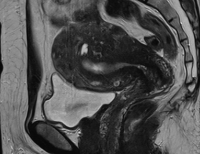

[산부인과 시술 제대로 알기]‘자궁선근증’ 자궁적출 대신 자궁보존 선택이 우선

매년 수많은 여성들이 자궁선근증을 진단받은 이후 자궁적출을 권유받고 있다. 하지만 최근 들어 자궁을 적출하지 않으면서 병변 부위만 선택적으로 제거하...

[산부인과 시술 제대로 알기]여성이 알아야 할 ‘자궁근종’ 대표적 증상부터 경과 관찰까지

가임기 여성에게 가장 흔하게 발견되는 자궁 종양인 ‘자궁근종’은 자궁의 근육층에 발생하는 양성종양이다. 강남권산부인과의원 권용일(대한산부인과학회...

[산부인과 시술 제대로 알기]여성 건강을 위협하는 ‘자궁근종’ 어떻게 관리해야 할까?

자궁근종은 자궁의 평활근 조직이 비정상적으로 증식하면서 생기는 양성 종양으로 여성들에게 흔히 나타나는 질환이다. 세종시 트리니움여성병원 이종표(대...